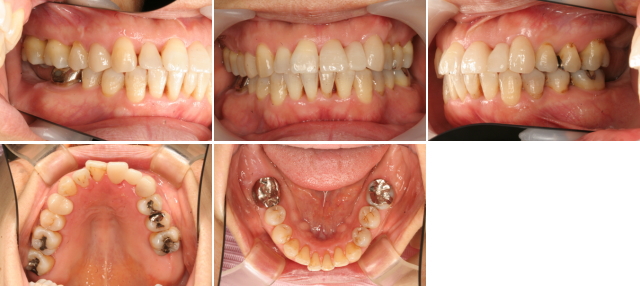

骨の再生を行ってから矯正治療を用いて、噛み合わせの治療を行いました。今後数十年の使用に耐えるこの患者さんの骨の作りに調和するように噛み合わせの再構築を行います。審美の回復も考えます。矯正治療期間は1年でした。

第二大臼歯は、初診時から歯周病で骨の支えを失いホープレスな状態でした。患者さんの骨の作りは、骨格2級であったため第二大臼歯はあえて製作しませんでした。

無くした歯を支える歯槽骨を再生し、また歯周ポケットも無い状態にでき、歯周病が完治しました。後は患者さんが毎日の普通の歯磨きを行うことで、再発する危険がとても少ない状態までもってこれました。